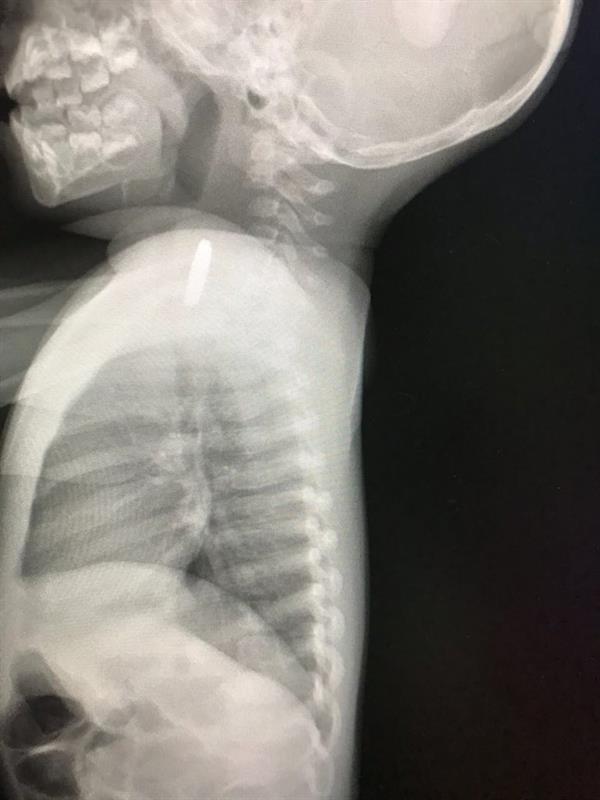

وفور وصول الطفلة إلى مستشفى القريات العام، تم إخضاعها لفحوص وأشعة أظهرت وجود جسم معدني أعلى المريء، فتم إدخالها للعمليات بالاستعانة بمنظار علوي كشف عن ابتلاعها بطارية ساعة أدت إلى خروج بعض المحتويات الكيميائية منها وتسببت في التهاب المريء.

وقالت "صحة القريات" إن فريقا طبيا بالمستشفى نجح في استخراج البطارية التي مكثت لمدة أسبوع، فيما غادرت الطفلة قسم التنويم وحالتها مستقرة.